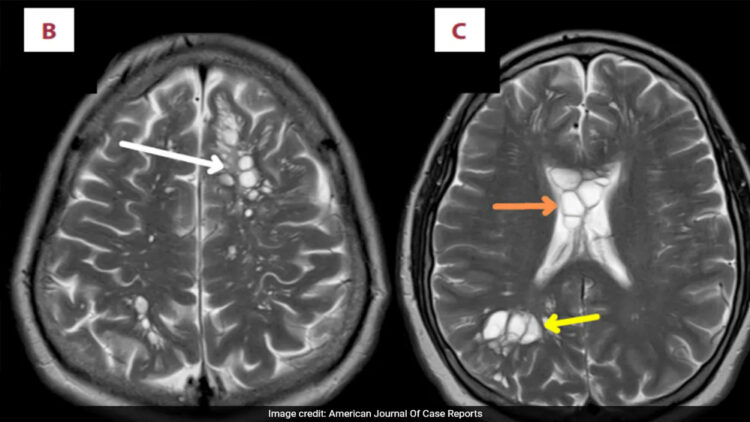

കഠിനമായ മൈഗ്രൻ ബാധിച്ച് ആശുപത്രിയിൽ എത്തിയ 52 കാരന്റെ തലച്ചോറിൽ നാടവീരകൾ കണ്ടെത്തി. ന്യൂയോർക്ക് പോസ്റ്റിന്റെ റിപ്പോർട്ട് അനുസരിച്ച് യുഎസ് പൗരനായ വ്യക്തിക്ക് കഴിഞ്ഞ നാല് മാസമായി തലവേദന അനുഭവപ്പെട്ടിരുന്നു. വേദന തീവ്രമായതൊടെ അദ്ദേഹം വൈദ്യസഹായം തേടി. സ്കാനിംഗിൽ തലച്ചോറിന്റെ ഇരുവശത്തുമായി ഒന്നിലധികം മുഴകൾ കണ്ടെത്തി, പിന്നീട് പരിശോധനയിൽ നാടവിരകളാണെന്ന് വ്യക്തമായി. രോഗിയെ ഉടൻ തന്നെ തീവ്രപരിചണ വിഭാഗത്തിലേക്ക് മാറ്റി ആദ്യ പടിയായി തലച്ചോറിലെ നീക്കം കുറയ്ക്കാനുള്ള ചികിത്സ ആരംഭിച്ചു.

ജന്തുക്കളുടെ ചെറുകുടലിൽ അധിവസിക്കുന്ന ഒരിനം പരാദ വിരയാണ് നാടവിര. ഇത്തരം വിരകൾ തലച്ചോറിൽ കണ്ടെത്തുന്നത് അത്യപൂർവ്വമാണെന്ന് അടുത്തിടെ പ്രസിദ്ധീകരിച്ച അമേരിക്കൻ ജേണൽ ഓഫ് കേസ് റിപ്പോർട്ടിൽ പറയുന്നു. യുഎസിൽ ഇത്തരം രോഗബാധ അധികം കണ്ടെത്തിയിട്ടില്ല.